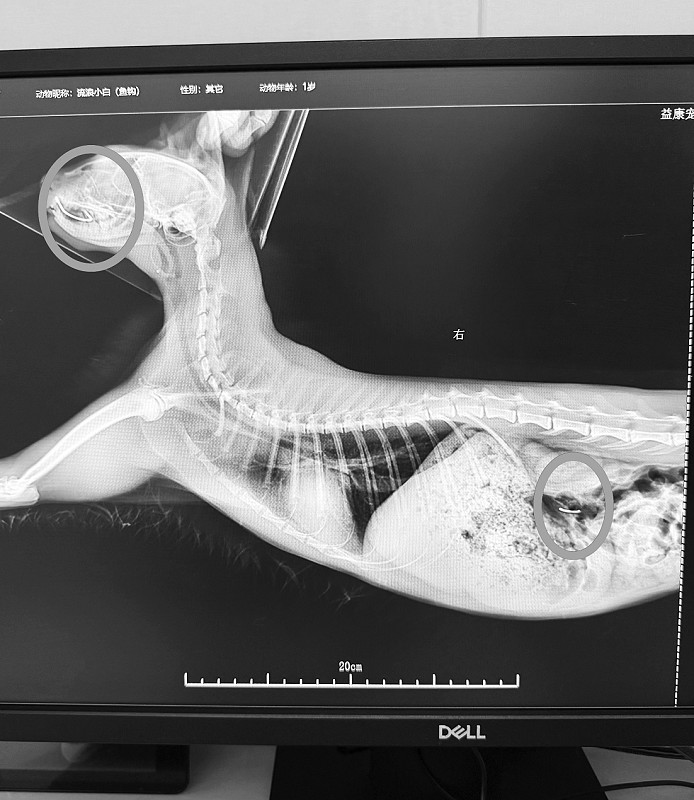

去年12月27日,宠物医院工作人员根据李女士的描述来到雕塑公园找到了小猫,历经半个多小时,工作人员成功抓住了小猫并送回医院救治。“李女士看到小猫嘴里是两个鱼钩,但到了医院时小猫嘴里只有一个鱼钩,我们担心另一个被吞到了肚子里,就拍了个片子,果然在小猫胃里发现了另一个鱼钩。”宠物医院随后决定免费为小猫进行手术,取出了小猫嘴角和胃中的鱼钩。目前,小猫正在恢复阶段,已无大碍,之后将由李女士与宠物医院商议对小猫进行安置。